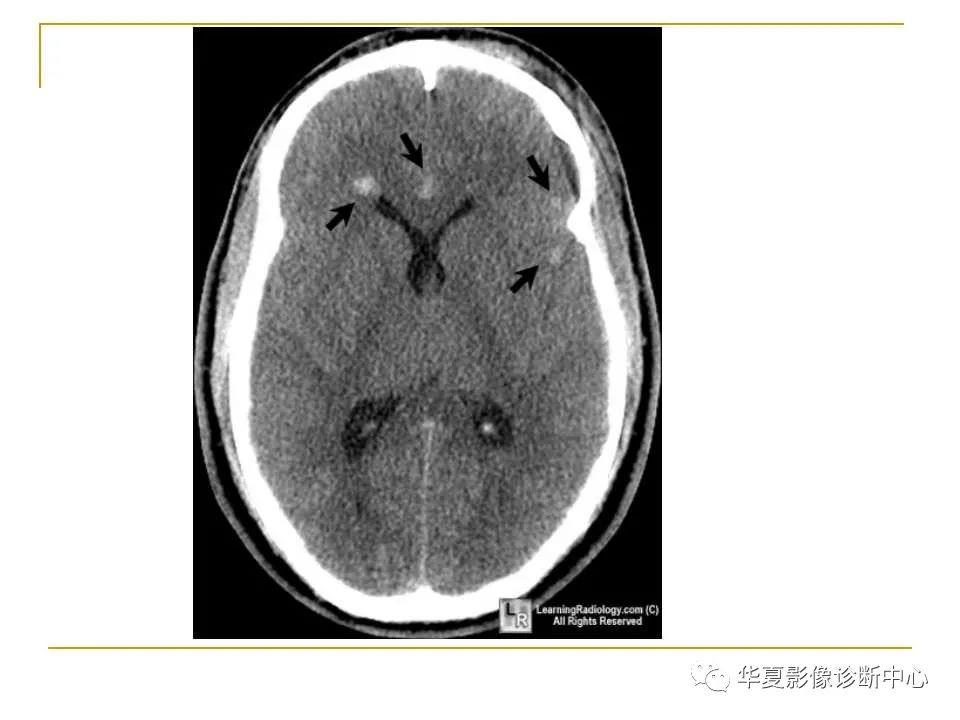

胼胝体解剖及病变大全